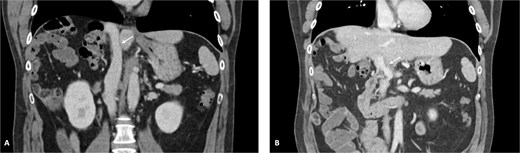

A 42-year-old asymptomatic male patient was referred with a suspicious liver mass detected on abdominal ultrasound (US). The US was made after a blood test revealed an isolated elevation of gamma-glutamyl transferase of 789 IU/l. Past and family history were unremarkable. Computed tomography (CT) scan revealed a large tumour measuring 12.6 cm occupying the right liver (Fig. 1 and Supplementary Video S1). Magnetic resonance confirmed a heterogeneous, ring-enhancing hepatic lesion with obliteration of the right hepatic vein (RHV), and invasion of the middle hepatic vein (MHV), PV, and the retrohepatic portion of the IVC. No metastatic lesions were present. Tumour markers and endoscopic exams revealed no alterations.

CT scan of the intrahepatic cholangiocarcinoma before chemotherapy. (A) Axial CT scan of the intrahepatic cholangiocarcinoma centred in liver segments 5, 7, and 8, with extension to segment 1 and invasion of the PV and IVC; (B) coronal CT scan view of the vascular relation between the cholangiocarcinoma and the IVC; and (C) vascular invasion of the PV.

The patient was discussed at a multidisciplinary meeting for suspected intrahepatic cholangiocarcinoma. Due to the tumour size and macrovascular invasion, the patient was proposed for neoadjuvant treatment. After a biopsy confirmed the diagnosis, the patient underwent three cycles of gemcitabine and cisplatin, resulting in a reduction of the cholangiocarcinoma from the maximum longitudinal diameter of 12.6 to 7.5 cm (Fig. 2). An extended right hepatectomy with resection and reconstruction of the PV and IVC using an APFP was then proposed.

CT scan of the intrahepatic cholangiocarcinoma after chemotherapy. (A) Axial CT scan showing cholangiocarcinoma diameter reduction after chemotherapy and (B) and (C) coronal CT scan view of the vascular relation between the cholangiocarcinoma, IVC, and PV.